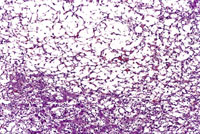

A relative discrete Ito cell tumor is present within this hepatic lobe; a higher magnification shows proliferation of stellate cells within the hepatic sinusoidal spaces.